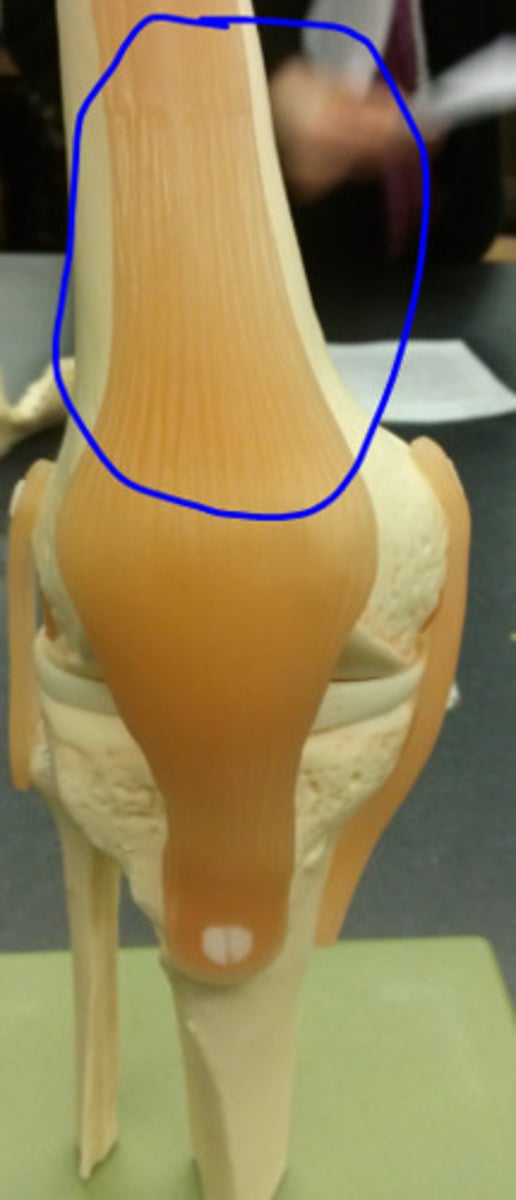

Tendon of Quadricepts

patella

Patellar Ligament